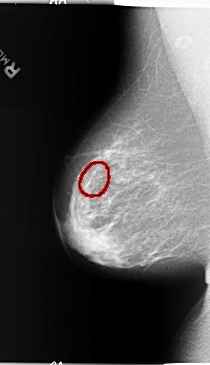

B_3095_1.RIGHT_MLO

RIGHT_MLO LINES 5840 PIXELS_PER_LINE 3352 BITS_PER_PIXEL 12 RESOLUTION 50 OVERLAY

FILE: B_3095_1.RIGHT_MLO.OVERLAY

TOTAL_ABNORMALITIES 1

ABNORMALITY 1

LESION_TYPE CALCIFICATION TYPE PLEOMORPHIC DISTRIBUTION SEGMENTAL

ASSESSMENT 4

SUBTLETY 3

PATHOLOGY BENIGN

TOTAL_OUTLINES 1

BOUNDARY